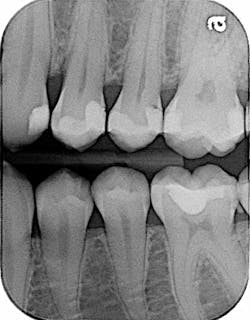

First, let me explain the technical importance of contacts in teeth. Patients hate food impaction. “Food gets caught right here,” my new patient said annoyingly the other day as he pointed in between his lower left molars. “I just had this filling placed a few months ago with a dentist my wife goes to, and now I have to floss it every time I eat, or I will have half my meal in there.”

Patients get angry over poor contacts and food traps. They don’t want to be bothered with the hassle of food impaction, and they may not even know that poor contacts are a source for further decay or even periodontal effects. So, it’s important that we get contacts right the first time. After all, it’s not that hard to check for open contacts at the end of treatment. This point of aggravation comes up in my office more times than I would like to think, which is why I want to review the importance of getting good contacts when we restore teeth, particularly when we complete fillings for patients.

Further, there usually is not much I can do to adapt in these situations, but contacts are different. I have only found a couple of ways to make a really good contact, especially when restoring cavities with composite restorations. I will skip amalgam fillings, because condensing amalgam tightly is not typically a problem; it’s usually the composite fillings that create problems for us.

Before ring systems came into use, traditional Tofflemire band holders and bands were used. I find the bands somewhat difficult to use, but you can make a contact if you use a softer, thinner band and some lateral condensing occurs on the band itself against the adjacent tooth. This precondensing and forming of the band helps ensure that a contact is formed.

I find the ring system design to be even more helpful. I have used the Garrison brand in the past, and I use Dentsply’s brand now. Both provide nice contours against the adjacent teeth; these contours help create optimal contacts. Sometimes, I still have to use a thin diamond or a 12-blade to shave off some of the interproximal overhangs to help guarantee that a smooth edge exists and a nice, popping contact sound occurs.